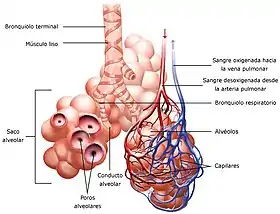

- Pulmones: Órganos cuya función es realizar el intercambio gaseoso con la sangre. Dentro de cada pulmón, el árbol bronquial se divide progresivamente dando ramificaciones cada vez más pequeñas. La tráquea da origen a los dos bronquios principales que se dividen en bronquios secundarios o lobulares. Cada bronquio lobular se divide en bronquios terciarios o segmentarios que se dividen en bronquiolos. El bronquiolo continúa el proceso de ramificación y da origen al bronquiolo terminal de donde parten los bronquiolos respiratorio que es donde se encuentran los sacos alveolares.

- Bronquio: Conducto tubular fibrocartilaginoso que conduce el aire desde la tráquea hasta los bronquiolos.

- Bronquiolo: Conducto que conduce el aire desde los bronquios hasta los alvéolos.

- Alvéolo: Los alveolos están situados al final de las últimas ramificaciones de los bronquiolos. Tienen la forma de pequeños sacos y son el lugar en el que se produce el intercambio de gases con la sangre. Su pared es muy delgada, pues está constituida por una capa unicelular, es decir formada por una única célula. Sumando los dos pulmones, el organismo humano dispone de alrededor de 600 millones de alveolos que si se desplegaran en su totalidad ocuparían una superficie de 60 m², esta enorme superficie es la que hace posible obtener la cantidad de oxígeno necesaria para las funciones vitales.[6]

Una vez que los alveolos pulmonares están llenos de aire tras el proceso de inspiración, el oxígeno tiene que difundirse hasta la sangre, mientras que el dióxido de carbono sigue el camino contrario, es decir pasa desde la sangre a los alvéolos pulmonares. Este proceso ocurre por un mecanismo de difusión simple motivado por un entrecruzamiento al azar de las moléculas que pasan desde donde se encuentran a más concentración hasta donde la concentración es menor. El fenómeno se debe a que las moléculas se encuentran en continuo movimiento y se desplaza en todas direcciones chocando y rebotando entre ellas reiteradamente. Existe una ley física según la cual cuando un gas se encuentra en una cámara cerrada y su concentración es diferente en los dos extremos, las partículas tienden a desplazarse desde donde la concentración es alta hacia donde es baja, llegando finalmente a una situación de equilibrio, proceso conocido como difusión simple.[11] En el aparato respiratorio la difusión se produce en el alveolo muy rápidamente, tiene lugar en los primeros 0,25 segundos de los 0,75 segundos del tiempo de circulación de la sangre a través de los capilares pulmonares.